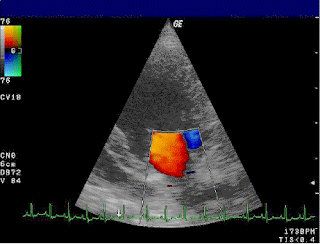

Mitral Stenosis Doppler Mitral regurgitation

Aortic regurgitation

mitral valve disease doppler

mitral regurgitation valve severe echocardiogram flail

aortic doppler regurgitation echocardiogram dog

doppler mr cw jet mitral regurgitation velocity echo valve echocardiogram vmax density ultrasound techniques contour cardioserv evaluation

tricuspid doppler regurgitation echocardiogram dog

mitral regurgitation valve echocardiography examination